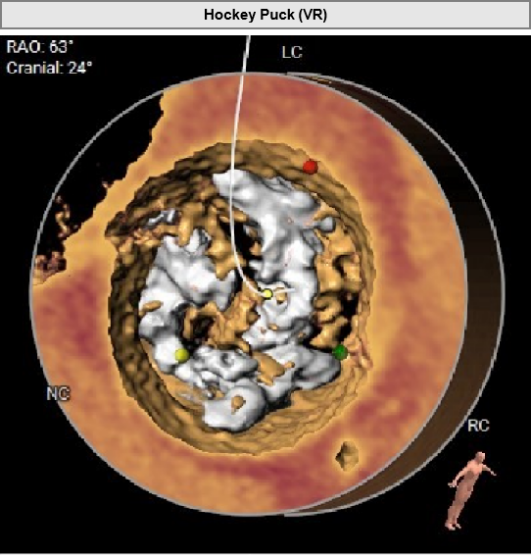

Type1型左右融合二叶式主动脉瓣。

瓣叶重度钙化合并增厚,钙化分布不均,主要集中于左右融合部。

HU419 积分3291mm²。

1. 主动脉根部极重度钙化,预估瓣膜受限严重,植入后可能存在钙化导致的瓣周漏;

2. 窦内钙化严重,瓣叶较长,球囊扩张时须注意瓣叶推移情况;

1. 患者主动脉瓣钙化严重,钙化灶较集中,推移难度较大,人工瓣膜展开形态可能较差,存在瓣周漏风险,在球囊预扩时应注意钙化灶运动情况